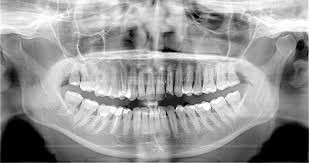

Thanks to its Field of View (FOV) of 8,5x8,5 cm, on the Rotograph Evo 3D the entire dental status can usually be visualized with a single, fast exposure, with images ready to be archived and treated with Dental Studio Software. Alternatively, should the user prefer to export the acquired images and use a 3rd party Software, Dental Studio can easily give as output the full set of slices in DICOM format. Differently, when the system is used in Panoramic or Cephalometric mode, the images are acquired directly in bidimensional format and not reconstructed from the 3D volume; as a consequence, they are therefore displayed with the typical standard 2D layout.